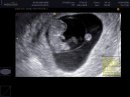

iwet001

20. feb 2010

Nase male kuriatko.